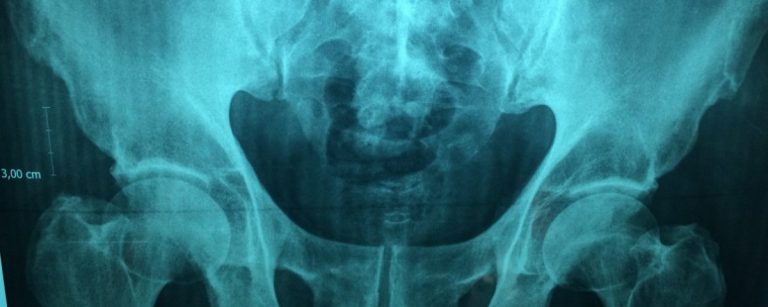

La osteoporosis es una enfermedad esquelética sistémica caracterizada por disminución de la densidad mineral ósea con alteraciones...